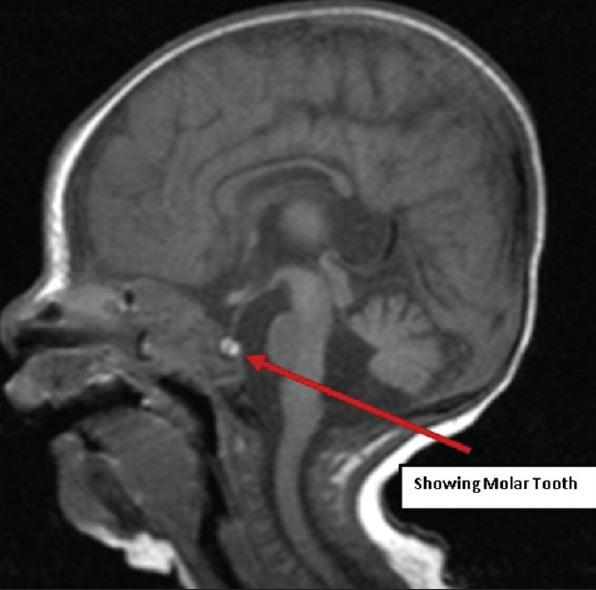

We report a case of 4 weeks old girl with a de novo interstitial deletion of the short arm of chromosome 3 (p13-p21) and clinical findings typical of proximal 3p deletion together with heart defects, choanal atresia, ear anomalies, central nervous system anomalies, renal anomalies and associated Joubert's syndrome (JS). Family history is unremarkable and parenteral chromosomes were normal. The clinical manifestations of the patient are compared with those of 11 patients previously described with a proximal 3p deletion. The additional JS features associated with this syndrome were described. This is the first case report in English literature describing 3p deletion associated with additional JS features.